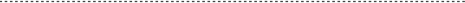

インプラント治療を安全に行うため、当院ではCT分析ソフト(SimPlant)を用い診断、シミュレーションを行っております。

以下の画像のように詳細な情報が得られることがお分かりいただけると思います。

安 全・安心・正確なインプラント治療

当クリニックでは安全・安心・正確なインプラント治療のためガイド手術を行っております。